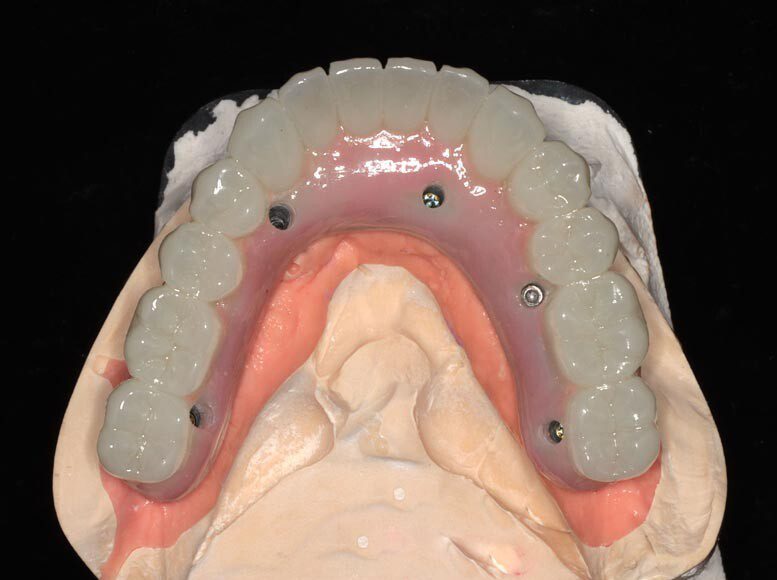

Lower teeth extracted, some bone removal lower, 8 upper implants, 5 lower implants, lower immediate temporary bridge.

Patient will continue to use his prior upper denture for three months as most of the upper implants were not stable enough for immediate temporary. After 3 months of healing, these implants will be ready for a fixed temporary bridge.

Three months post, first surgery the patient returns for implant uncovering and these are the impression copings preparing for the fixed temporary bridge.